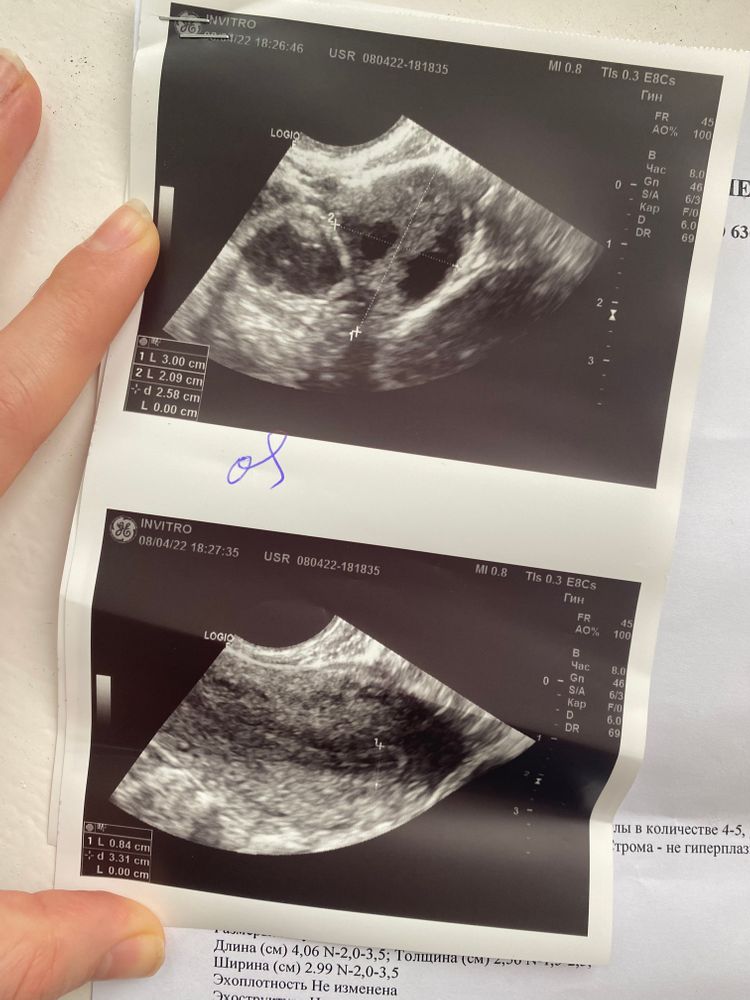

Всем приветик. Девочки , скажите пожалуйста у кого была толщина эндометрий после овуляции 8,4 можно ли с такой толщиной родить ? У меня не регулярный цикл , вечно скачет. Сделала тест на овуляцию на 20 дц (07.04.2022) тест показал овуляцию. Вчера (08.04.2022) ходила на фолликулометрию, врач сказал , что все хорошо овуляция была и видеть очень хорошее желтое тело, но вот толщина эндометрий ее расстроил ( она сказала , что на 21 дц толщина не соответствует( ну хотя сказала , что многие рожают. Но я что то переживаю (((

Точно такой же был эндометрий на след день после О, врач сказала что нормальный, сказала пробовать. Но у нас не получилось в тот цикл, не знаю из-за чего. Овуляция у меня кстати на тот же день была, как и у вас. Всё получится у вас!)